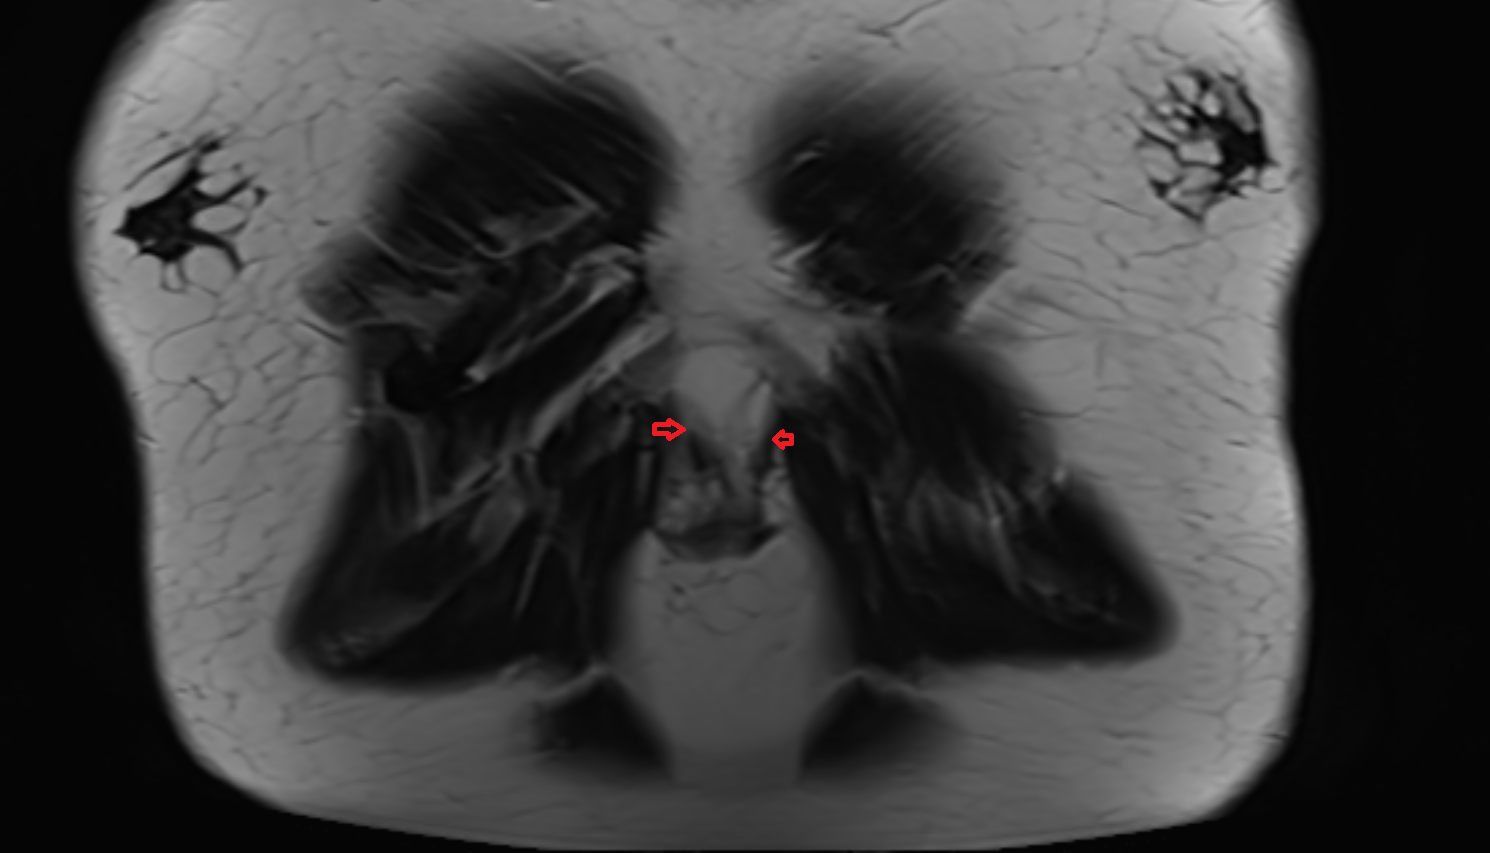

- Medial meniscus

- Lateral meniscus